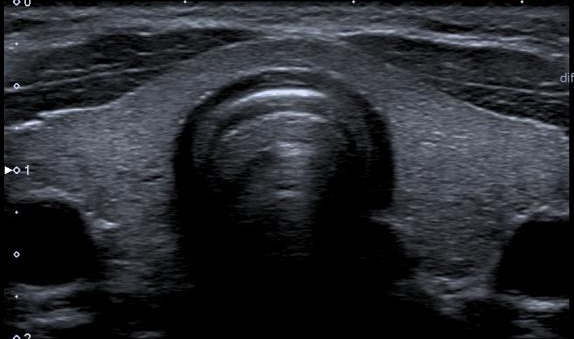

Ultrasound

ULTRASOUND